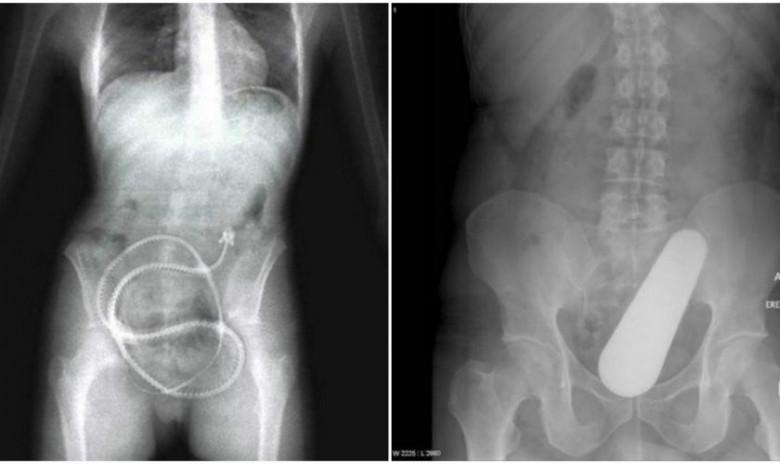

LifestyleՌենտգեն ապարատի ճառագայթների ներքո երբեմն ոչ միայն ներքին օրգաններն ու ոսկորներն են երևում, այլ նաև օտար մարմինները, որոնք հայտնվել են մարմնում։ Տարբեր առարկաների՝ օրգանիզմում հայտնվելը կարող են ունենալ ամենասարսափելի ու անհավանական պատմությունները։ Այս լուսանկարներում հենց նման արտասովոր դեպքեր են։